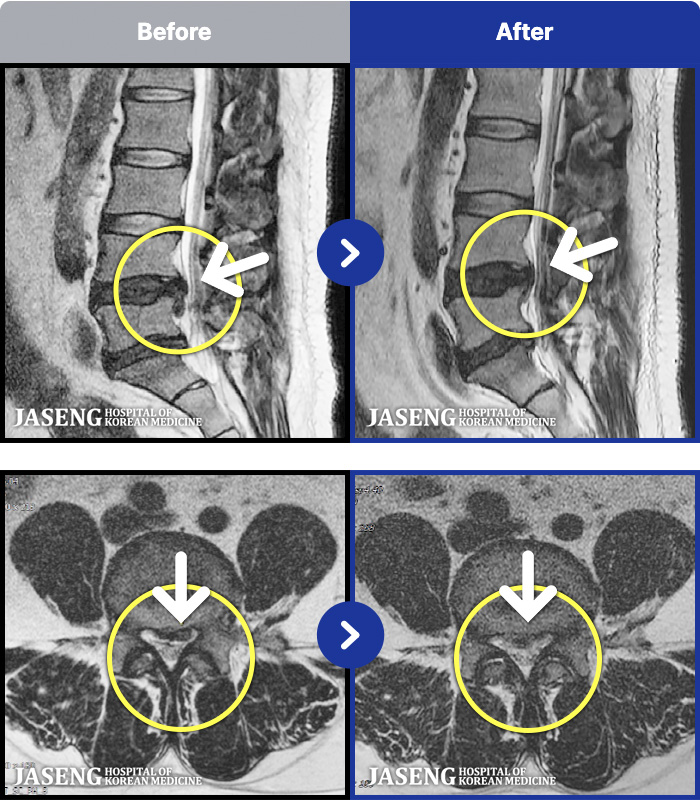

62 MRI ũ ʸ Ȯϼ.

ȯںп Ǹ ǿ ԿǾ, ο ġ ۿ Ƿ ġḦ Ͻñ ٶϴ.